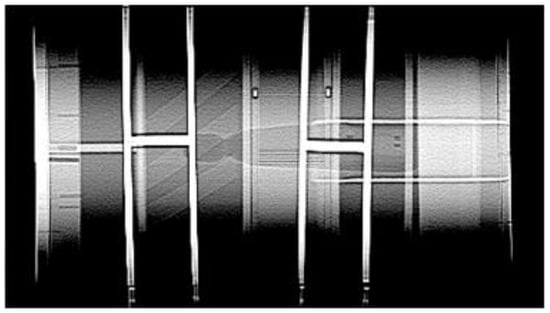

For spatial resolution, the CTA YOLOv8 results are shown Figure 11. The mean average precision (mAP) was used as the performance metric to assess object detection accuracy, as the task was to detect each object as either a pass or non-pass.

Figure 11. (a) Sample nonpass images of CTA-YOLOv8 applied for spatial resolution; (b) Sample pass images of CTA-YOLOv8 applied for spatial resolution.